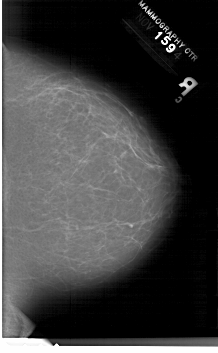

A_1202_1.LEFT_CC

LEFT_CC LINES 6871 PIXELS_PER_LINE 4261 BITS_PER_PIXEL 12 RESOLUTION 43.5 OVERLAY